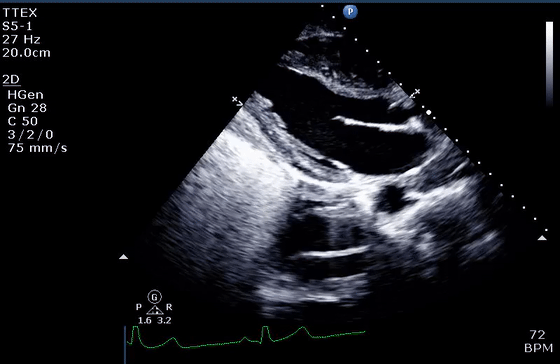

2、混响伪像

混响伪像违反了回波在一次反射后返回探头的假设。理论上,当超声波从探头发射时,反射波直接传输回探头,进行一次往返。实际上,第一次反回到探头的声波又从探头的平滑面再次反射,在两倍于第一反射器的距离处产生伪像。在心动周期期间,伪影的运动与真实结构的运动平行,但幅度更大(通常是两倍)(视频1-3)。

图2 (A,B)混响假象的理论成因(视频1)。第二反射界面可以是探头本身(A ),导致到探头两倍距离处的混响,或者是位于第一反射器上方的另一个强反射器(B)。

(C)胸骨旁长轴切面中的混响伪影似为左心房中的肿块(箭头)。对肿块的详细分析表明,它是钙化主动脉瓣环的反射(箭头),肿块正好出现在距离传感器两倍的距离处(视频2)。

(D)“多层”主动脉钙化(箭头)下方典型的“阶梯式”反射(实心箭头),作为第一和第二反射层(视频3)。也可以观察到强反射心包下的彗尾反射(空箭头)。